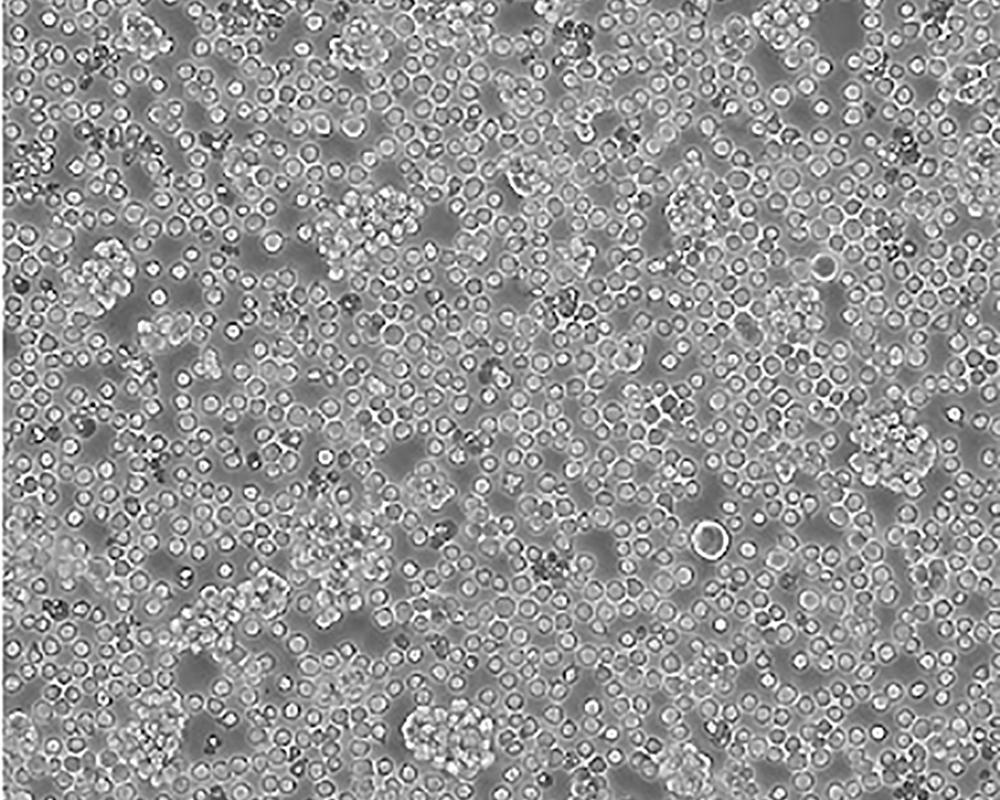

Jurkat, Clone E6-1 [Jurkat E6-1]

人T淋巴細胞白血病細胞

急性T淋巴細胞白血病;男性

suspension

lymphoblast

該細胞是Jurkat-FHCRC細胞株(Jurkat細胞株的衍生)的一個克隆。Jurkat細胞株來源于一個14歲男孩的外周血。經(jīng)佛波酯和外源凝集素或抗T3單克隆抗體誘導后可產生大量IL-2(IL-2的產生需兩種類型的誘導劑);表達T細胞受體、CD3